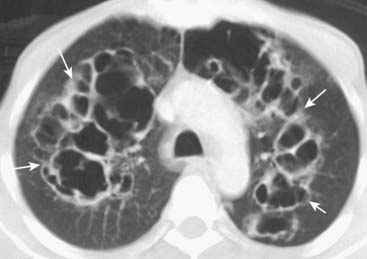

image With CT, findings of COPD may include focal areas of low density in which the cystic areas lack visible walls except where bounded by interlobular septa. CT is helpful in evaluating the extent of emphysematous disease and in planning for surgical procedures designed to remove bullae to reduce lung volume.

image

Figure 12-22 Types of emphysema.

A, Centriacinar (centrilobular) emphysema features focal destruction limited to the respiratory bronchioles and the central portions of the acinus (solid white arrows). It is associated with cigarette smoking and is most severe in the upper lobes. B, Panacinar (panlobular) emphysema involves the entire alveolus distal to the terminal bronchiole, is most severe in the lower lung zones, and generally develops in patients with homozygous alpha1-antitrypsin deficiency. C, Paraseptal emphysema is the least common form, involves distal airway structures, alveolar ducts, and sacs, tends to be subpleural, and may cause pneumothorax.